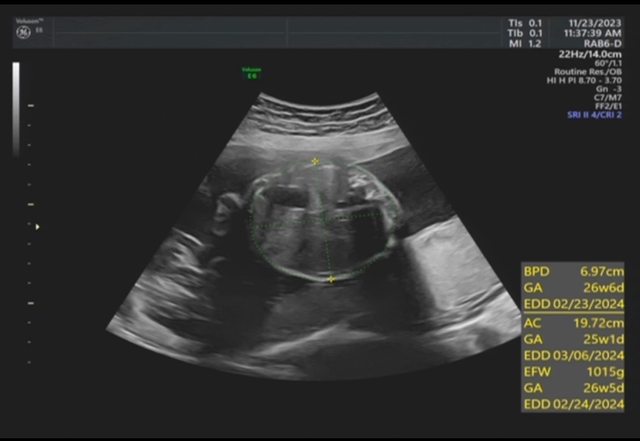

昨天去產檢,醫生覺得寶寶的胃偏大之後要注意觀察 我搜尋了一下好像只有看到胃太小的文,請問大家有沒有遇過類似情況? 我後來看了一下22週的高層次照片,那時候寶寶也是胃大大的,但那時只說是寶寶可能剛 吃飽 https://i.imgur.com/amlKp09.jpg

每一胎的狀況真的不一樣,這次第二胎先歷經羊水少週數小三週,到現在追到剩小一週, 但昨天醫生又提醒胃好像偏大,只希望二寶可以健康平安出生~ -- ※ 發信站: 批踢踢實業坊(ptt-club.com.tw), 來自: 101.12.24.40 (臺灣) ※ 文章網址: https://ptt-club.com.tw/BabyMother/M.1700797726.A.8D2